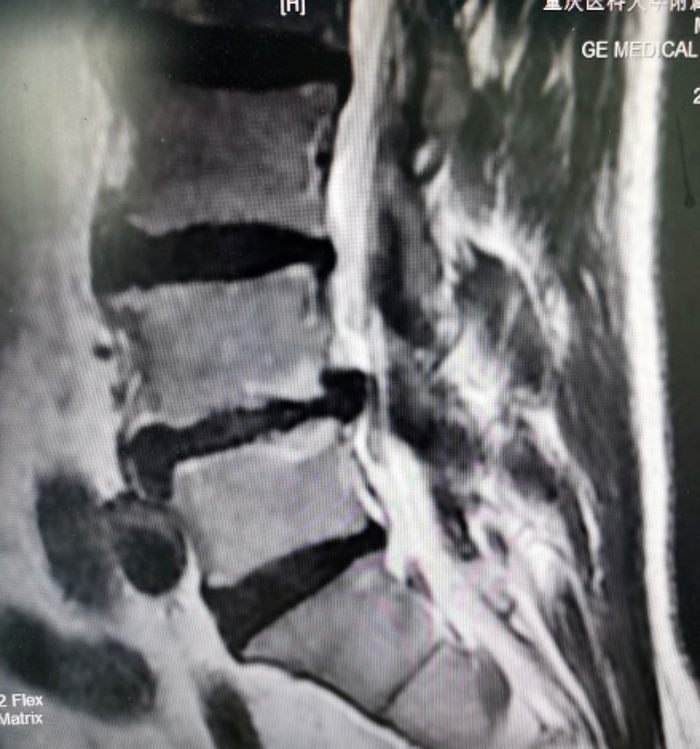

术前腰椎MRI提示:腰4/5椎间盘突出伴侧隐窝狭窄/图源 重医附三院

孙红振医生和同事为邹先生完善术前检查和评估,并组织病例分析和术前讨论,考虑患者存在腰椎间盘突出伴侧隐窝狭窄,腰椎不稳,椎间隙高度明显丢失等。若采取传统开放减压融合手术需对患者椎旁软组织进行广泛剥离,手术创伤大,手术风险高,老年患者术后恢复慢且潜在并发症多。为彻底解除神经压迫,重建脊柱稳定性,尽可能降低患者医疗费用,缩短住院及卧床时间,经与患方充分沟通,孙红振医生团队决定实施微创通道下经椎间孔入路腰4/5和腰5/骶1椎体间融合术(MIS-TLIF)。

术后第二天,邹先生就在腰围保护下离床自由活动,腿痛完全缓解,术后第四天出院。患者及家属对手术效果赞不绝口。